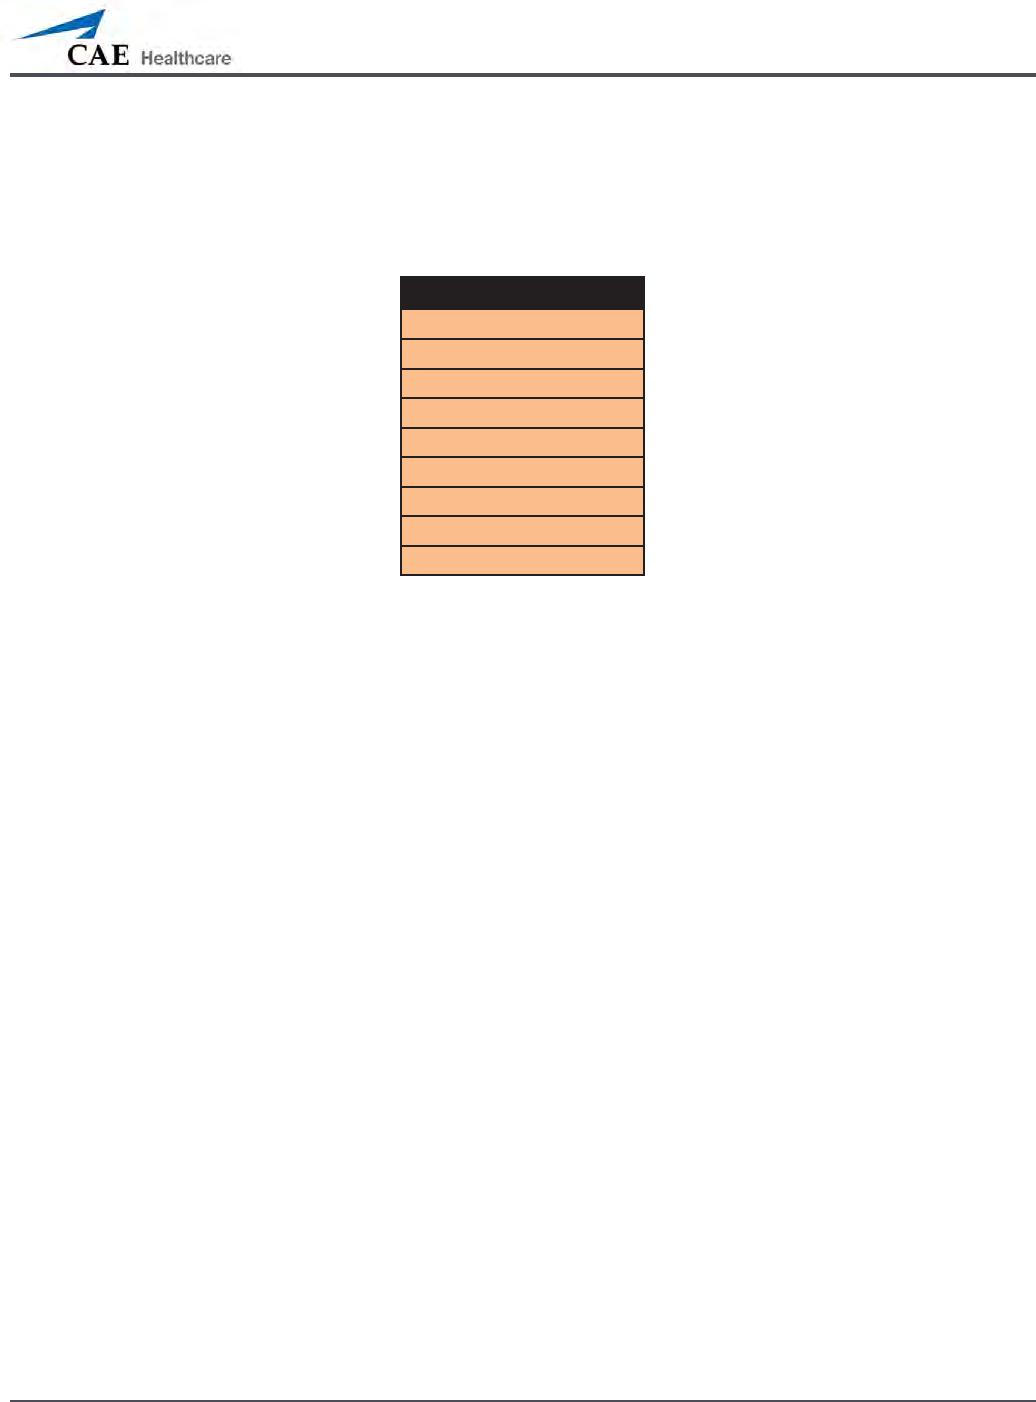

Breath Sounds

Normal

Crackles

Diminished

Gurgling

Pleura Rub

Rhonchi

Wheezing

Click any one of the Breath Sounds drop-down menus that each control one of four

quadrants to change the type of sound. Click and drag the slider for each location to adjust the

volume.

A patient must be running on a METIman simulator for any sounds to be available.

By default, Normal breath sounds are heard.

Breath sounds can be adjusted by clicking the Sounds button on the Run screen. When the

Sounds panel appears, select Breath Sounds.

Heart Sounds

Normal S1-S2

S3

S4

S3 and S4

Early Systolic Murmur

Mid Systolic Murmur

Late Systolic Murmur

Pan Systolic Murmur

Late Diastolic Murmur

Heart sounds can be adjusted by clicking the Sounds button on the Run screen. When the

Sounds panel appears, select Heart Sounds.

The Heart Sounds Menu

Click the Heart Sounds drop-down menu to change the type of sound. Click and drag the

slider to adjust the volume.